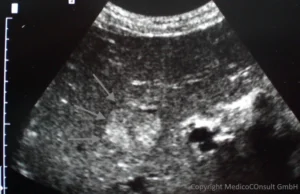

Sonographie: Charakteristisch für ein Hämangiom ist ein homogen echoreicher, scharf begrenzter Bezirk. Kavernöse Hämangiome dagegen können auch relativ reflexarm sein. Bei Unsicherheit, z. B. wenn die Differenzialdiagnosen eines hepatozellulären Karzinoms, einer fokalen Mehrverfettung, einer Tumormetastase oder eines Hämangioendothelioms im Raum stehen, können eine Kontrastmittelsonographie, Computertomographie (CT) der Leber und MRT helfen, die Diagnose zu klären.

Die Kontrastmittel-Sonographie lässt bei einem größeren Hämangiom ein „Irisblendenphänomen“ erkennen: Das Kontrastmittel flutet von außen an und erreicht durch Ausbreitung vorn dort das Zentrum. Der Herd blasst anschließend gegenüber dem normalen Lebergewebe verzögert ab (siehe hier). Unter den verschiedenen Formen gibt es solche, die eine Kapsel aufweisen können, zystisch aussehen, durch Verkalkung von Einblutungen konkrementartige Schallschatten werfen oder durch Verfettungen reflexreich erscheinen.